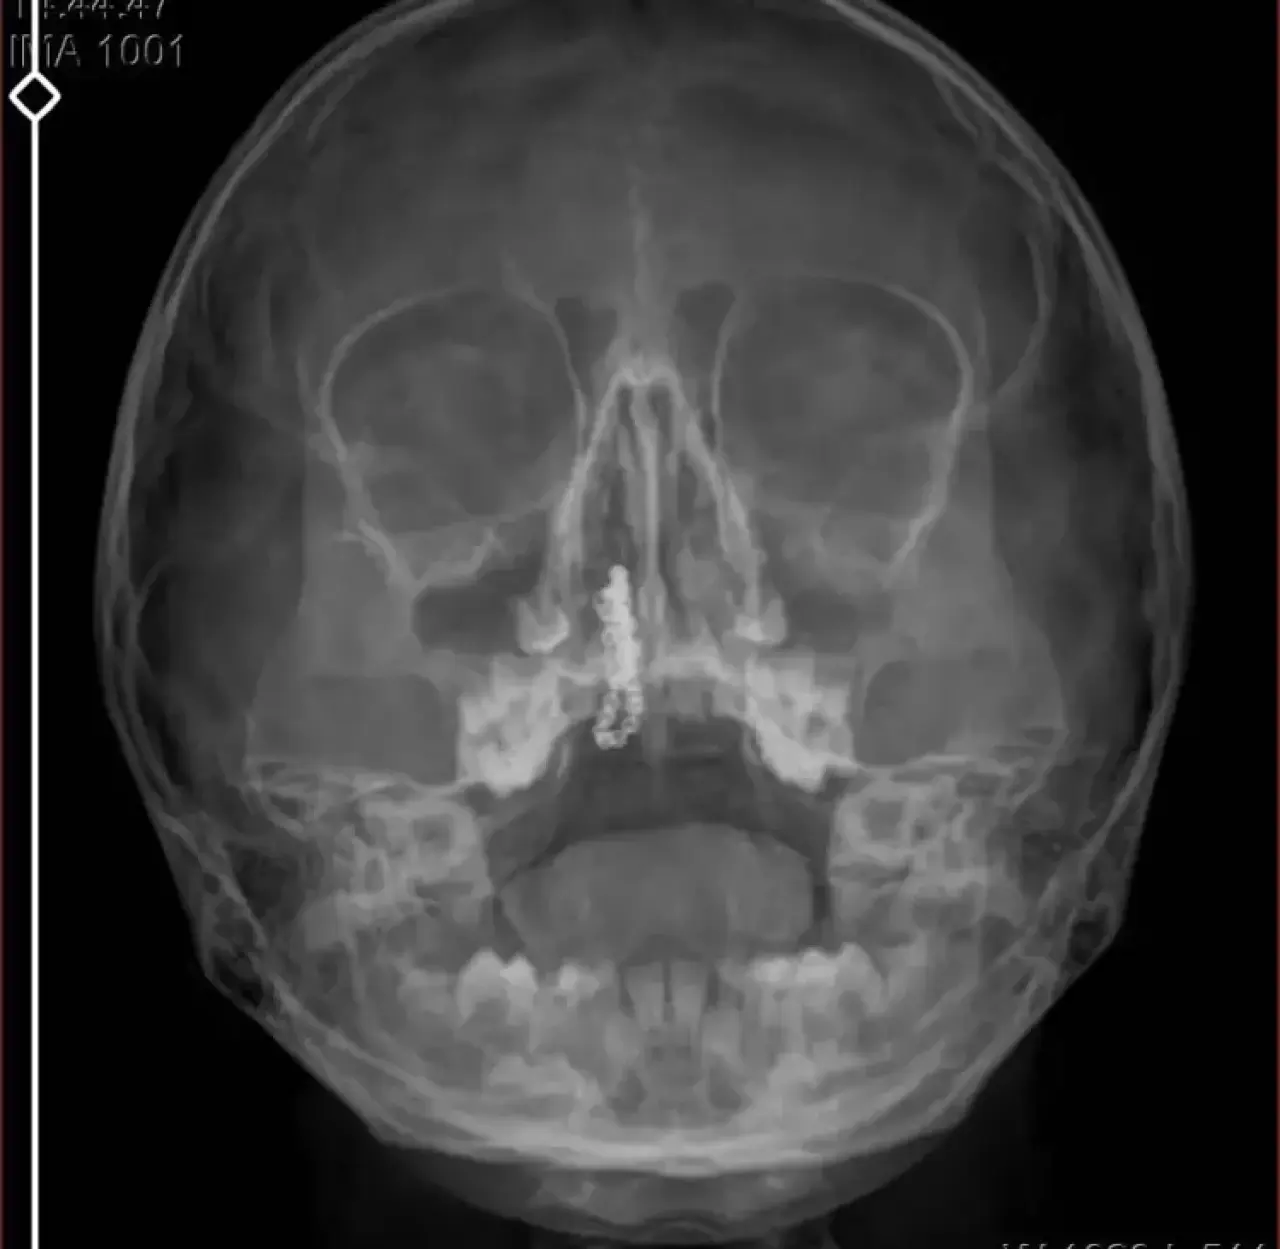

Röntgen sonucu burnunda metal cisim olduğu fark edildi

Devlet hastanesindeki doktorun incelemesi ve kapsamlı röntgen çekilmesi sonrası Polen'in burnunda metal cisim olduğu fark edildi. 2 yıldır burunda kaldığı değerlendirilip, küçük top şeklinde tırnak makası zinciri olduğu belirlenen cisim, başarılı ameliyatla çıkarıldı. Bir süre tedavisi sürdürülen Polen, sağlığına kavuşunca taburcu edildi. Özel hastane yetkilileri, konuyla ilgili açıklama yapmazken; aile suç duyurusunda bulunacaklarını söyledi.

Kızının ameliyat sonrası durumunun iyi olduğunu söyleyen Tekin, "İnanır mısınız bize 'Evde soba mı yanıyor? Acaba kömür isten dolayı mıdır bu?' dendi. Böyle bir şey olabilir mi? Ameliyattan çıkan parmağım kadar zincir. Devlet hastanesindeki doktor da 'Bu nasıl gözden kaçılabilir? Böyle bir pozisyon nasıl görülmeyebilir?' yorumunda bulundu. Allah'a şükür olsun atlattık. Şu anda durumu, vaziyeti iyidir. Ben şuna inanıyorum doktor da bir şans işidir. Bakın paramızla özele gideriz ya hani bizde, daha iyi ilgilenirler. Oysa devlet hastanesindeki doktorumuz olayı meydana çıkardı" diye konuştu.